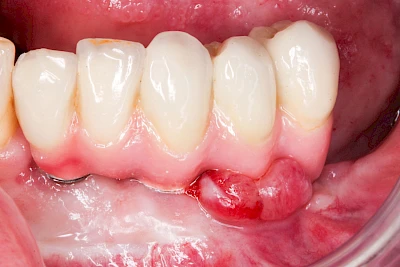

Sonderform: Fistel

Bei einer Fistel hat sich meist eine Entzündung (manchmal auch Erreger selbst) z. B. aufgrund von Karies oder aufgrund eines Unfalls über den Zahnnerv und die Wurzelspitze (Apex) in den umliegenden Knochen ausgebreitet (apikale Parodontitis) und schnell einen Weg durch den umgebenden Knochen und die aufliegende Schleimhaut in die Mundhöhle gebahnt.

Fisteln sind in der Regel nicht schmerzhaft und fallen häufig als kleine Öffnung weiter entfernt vom Zahnfleisch nahe der Umschlagfalte auf. Aus der Fistelöffnung entleert sich spontan gelbliches Sekret (Eiter) oder es lässt sich mit dem Finger ausstreichen. Manchmal beschreiben die betroffenen Menschen immer wieder einen komischen Geschmack im Mund.

Im fortgeschrittenen Stadium kann die Schleimhaut sich weiter zurückgezogen haben und die Wurzelspitze sichtbar sein. In der Regel treten bei Fisteln keine Schwellungen auf, weil sich die Entzündung nicht im Gewebe ausbreitet.

Bei Fisteln sollte zeitnah der Zahnarzt kontaktiert werden. Treten Fisteln im Zusammenhang mit Schwellungen auf, ist sofort der Zahnarzt zu kontaktieren. Ist der Zahnarzt nicht zu erreichen und es verschlechtert sich der Allgemeinzustand (z. B. Fieber) sollte der Notarzt gerufen werden.